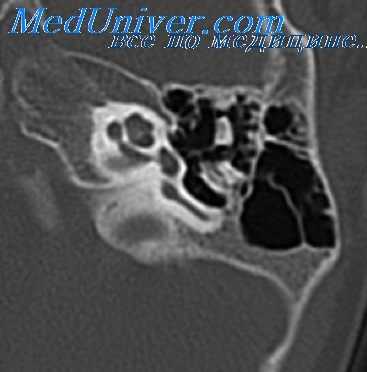

Диагностика опухоли уха в барабанной полости часто затруднительна и становиться возможной только при ее распространении на окружающие структуры. Заподозрить злокачественную опухоль в ухе на раннем этапе можно при обнаружении на рентгенографии значительных костных разрушений, не соответствующих обычному течению хронического среднего отита.

Определение распространенности опухоли уха проводится при помощи КТ черепа, КТ и МРТ головного мозга, ангиографии, фарингоскопии и других обследований.

Диагноз устанавливают на основании отоскопии, рентгенографии черепа и биопсии с последующим гистологическим исследованием. При проведении отоскопии обнаруживаются обширные, легко кровоточащие разрастания. На рентгенограммах при распространенных процессах выявляются очаги деструкции. Для уточнения объема поражения больных раком уха направляют на консультацию к неврологу, назначают МРТ головного мозга и другие исследования. Дифференциальную диагностику проводят с хроническим гнойным отитом, остеомиелитом височной кости, сифилисом, туберкулезом и каротидной хемодектомой.